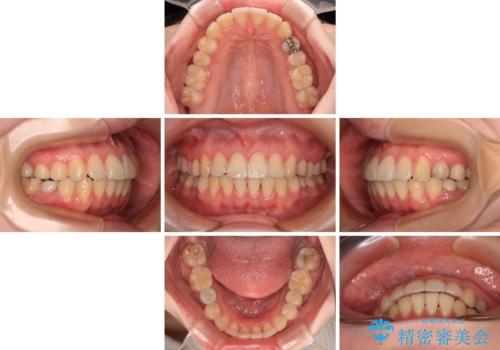

開咬と前方に飛び出した前歯 インビザラインによる矯正治療

舌の突出癖改善のトレーニングをしっかりと行っていただき、上下前歯が接触する咬み合わせを達成することができました。

- 1年5ヶ月

- 5-10回